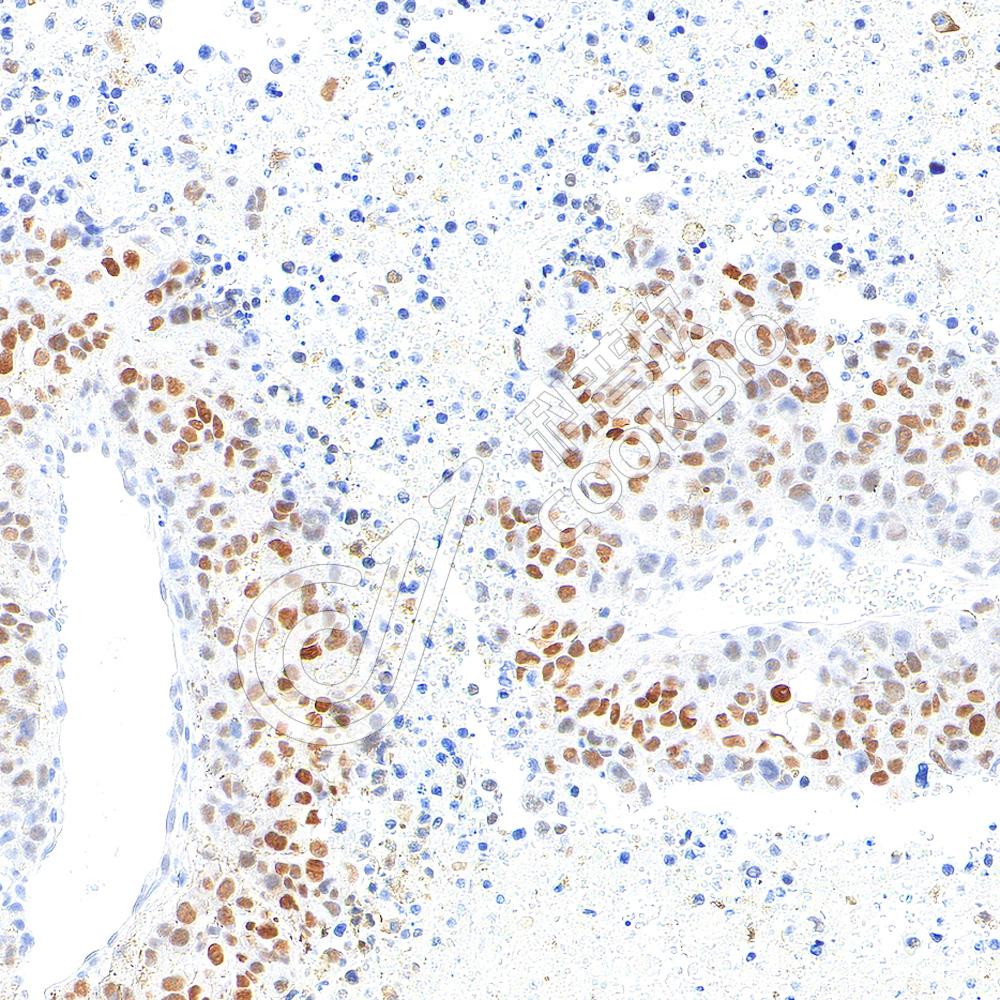

IHC检测HIF-1 alpha蛋白(货号 K5454017).

样品: 小鼠B16细胞皮下核-M模型, 4%多聚甲醛 (货号KSG1101) 固定12-24小时.

抗原修复: Tris-EDTA抗原修复液(pH 9.0) (KSG1203), 98℃, 20分钟.

—抗: 1: 900稀释, 4℃ 孵育过夜.

二抗: S-vision免疫组化多聚二抗(山羊抗兔),即用型 (货号KB3906), 室温孵育20分钟.